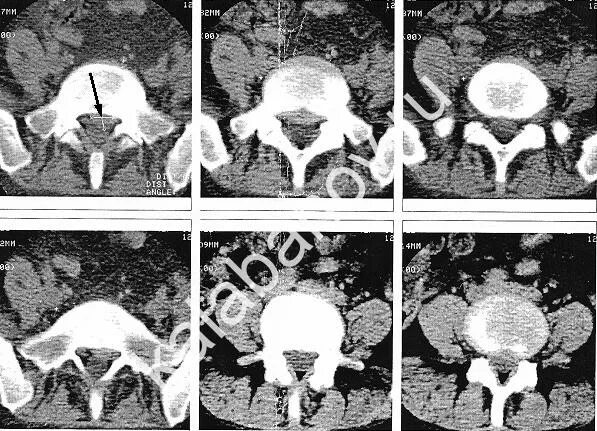

Медианно парамедианная протрузия диска